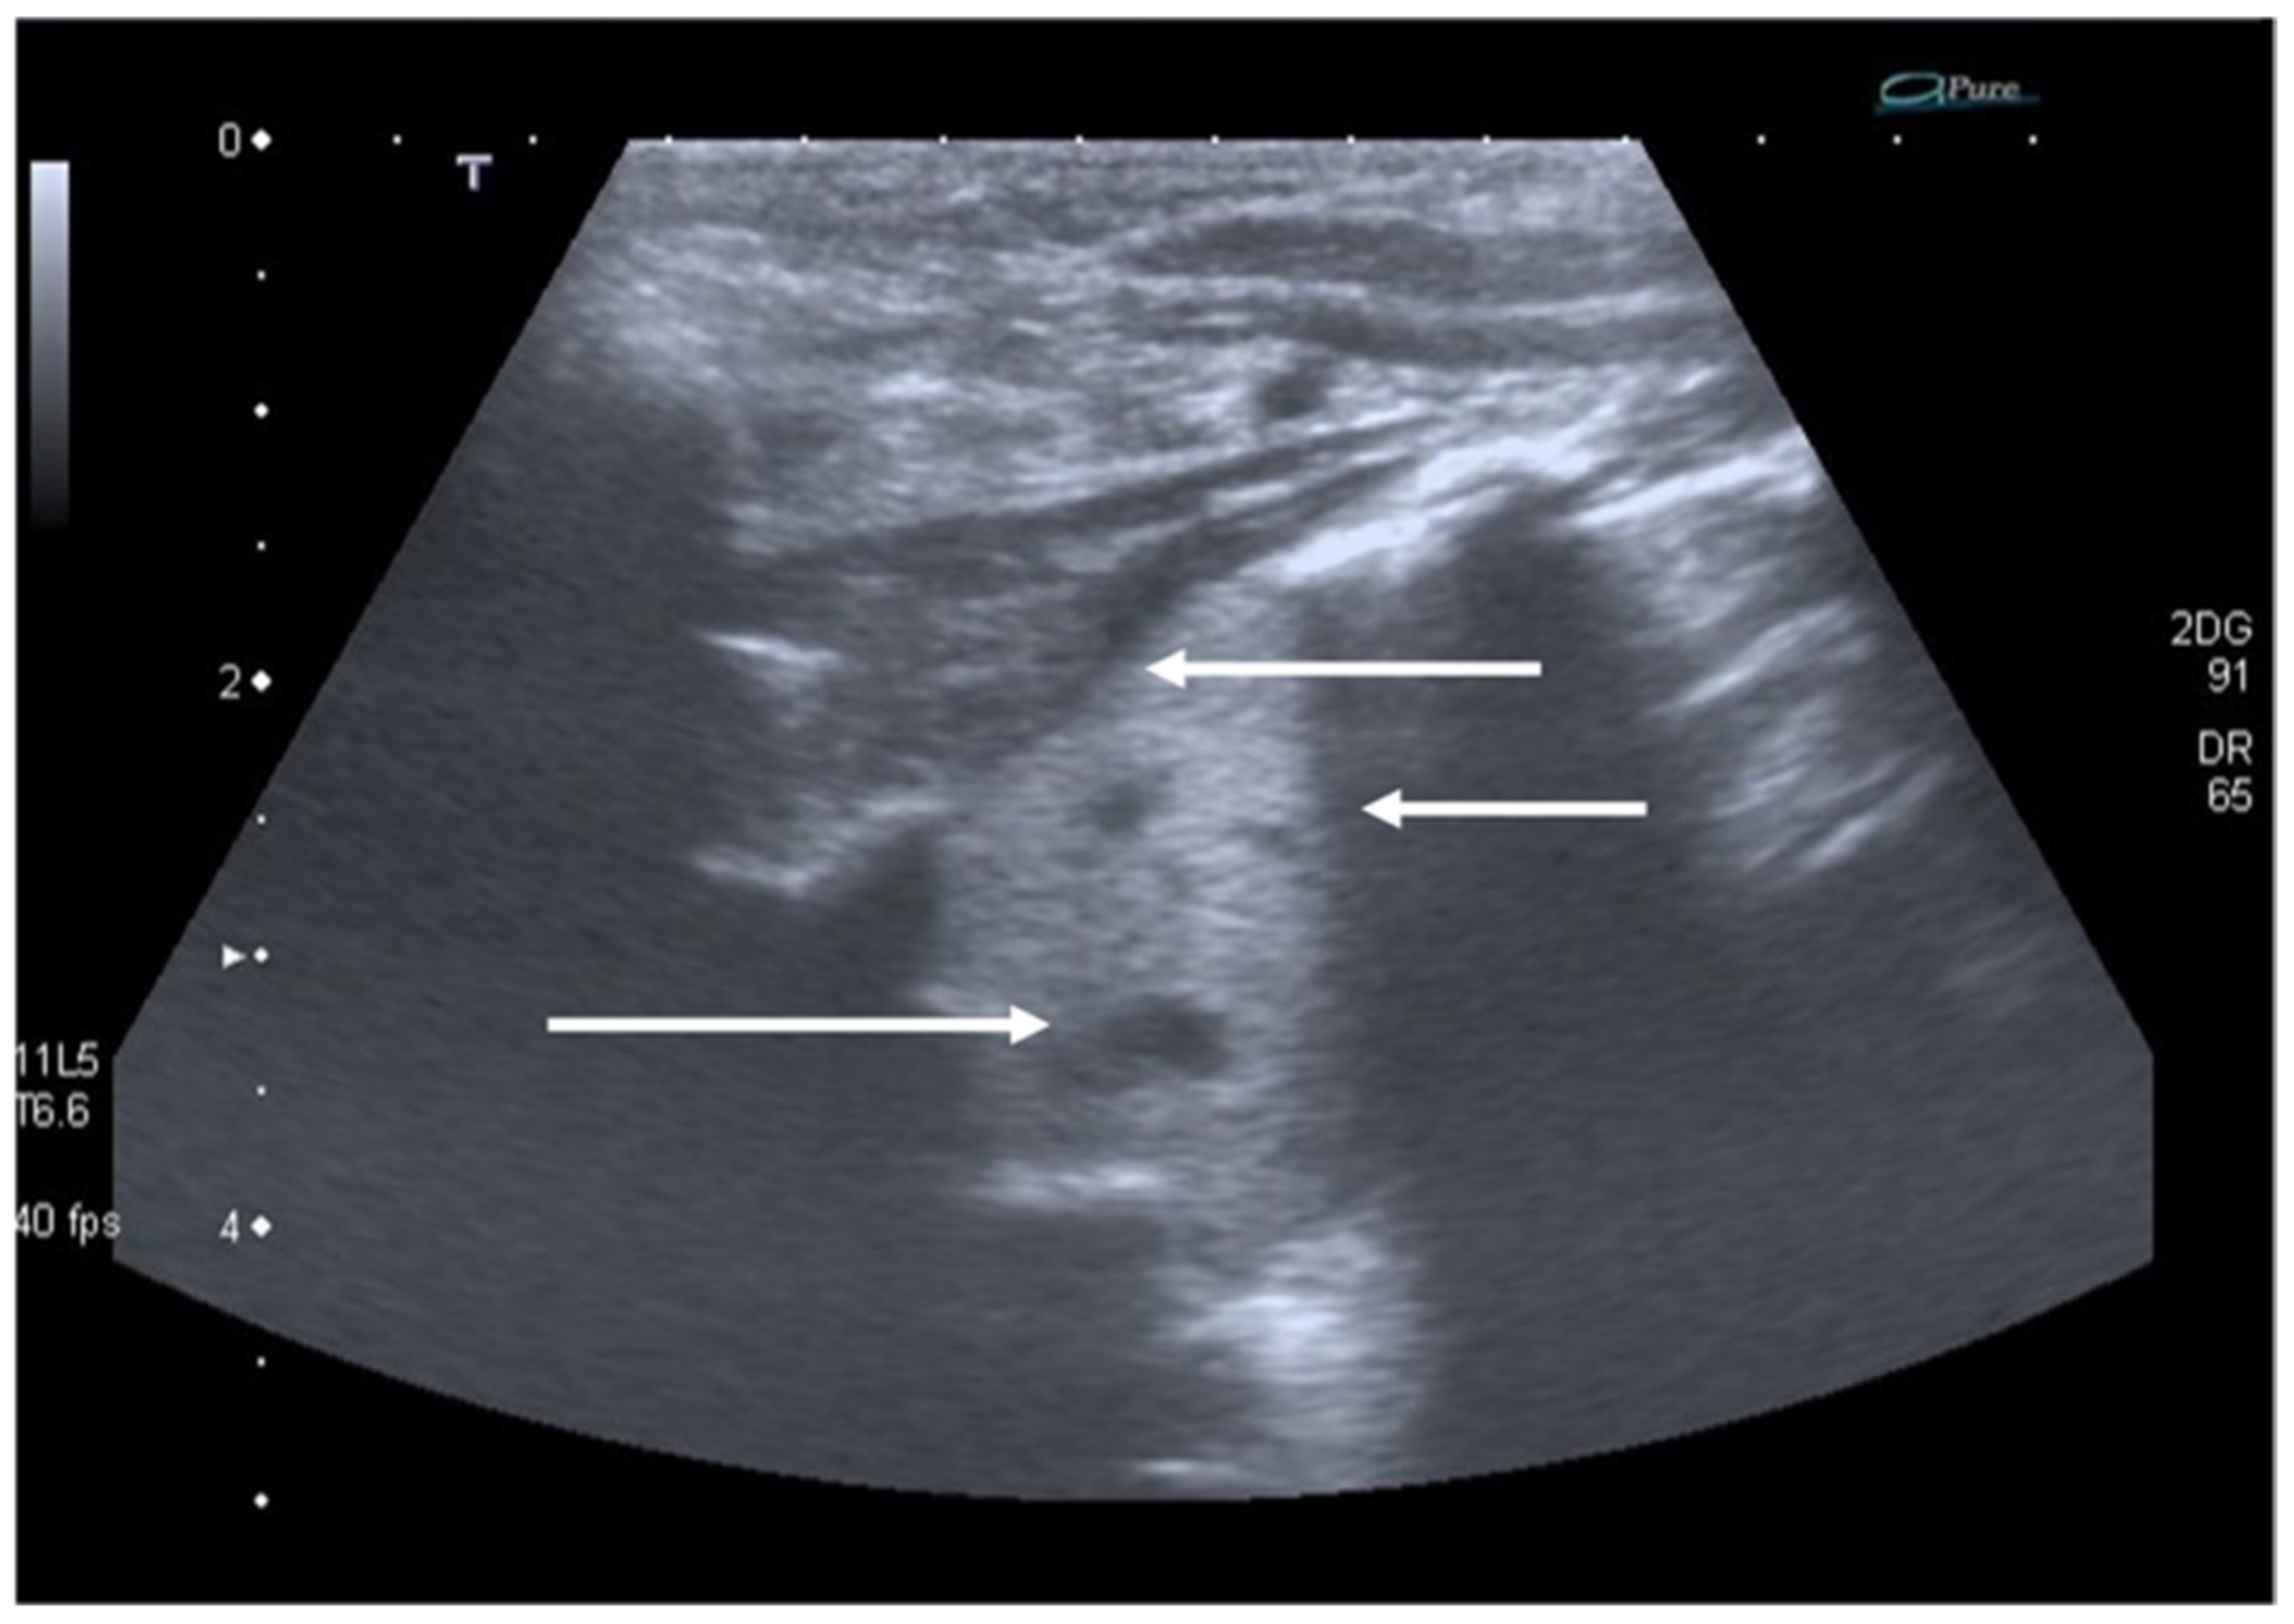

The role of LUS in identifying pleural effusion is also well established [53]. In fact, many studies have evaluated the efficacy of lung ultrasound in the diagnosis of pleural effusion, calculating its sensitivity and specificity, which have often been close to 100% [54]. These studies have confirmed the superiority of ultrasound over CXR in pleural effusion detection due to the capability of ultrasound to detect fluid collections as small as 20 mL [55]. Usually, pleural effusion can be visualized by ultrasound as a dark and anechogenic region located above the diaphragm that also determines the disappearance of the mirror image of the liver and spleen in the lung fields, which can be visualized in the healthy lung (Figure 10) [14]. Ultrasound also allows quantifying the amount of fluid accumulated in the pleural cavity well and characterizing the fluid collection differentiating a transudate from an exudate. The transudate is characterized by a dark image without internal echoes, representing an uncomplicated collection, while an image characterized by a septate or multiloculated corpuscular fluid collection is typical of the exudate [14].

Figure 10.

Anechogenic fluid collection above the diaphragm suggestive of pleural effusion (white arrows).